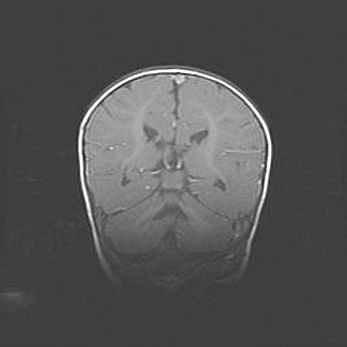

Открытая гидроцефалия.

Возраст: 9 месяцев 12 дней

Вес: 6800 г

Пол: мужской

Окружность головы: 41,5 см

Срок гестации: 28 недель

Гидроцефалия головного мозга у новорожденных имеет характерный признак: опережающий рост окружности головы приводит к визуально хорошо определяемой гидроцефальной форме сильно увеличенного в объёме черепа. Детские неврологи определяют следующие симптомы гидроцефалии у грудничков: выбухающий напряжённый родничок, частое запрокидывание головы, смещение глазных яблок к низу.